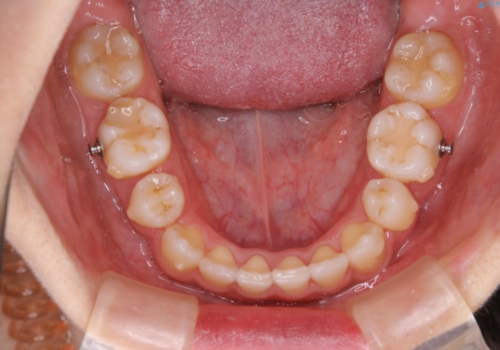

ブラケット除去直後に目立っていた下顎前歯部の大きなブラックトライアングルもあまり目立たなくなり、大変喜んでいただけました。

- 元々は海外でワイヤー矯正を行っていたが、コロナ禍で海外への往来が難しくなり、治療を中断せざるを得なくなってしまった方です。

ご本人のご希望により、インビザラインによる治療を行いました。